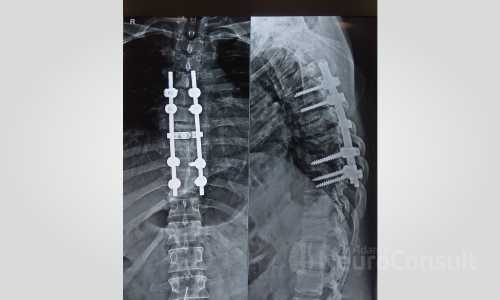

My Cases Studies & Work